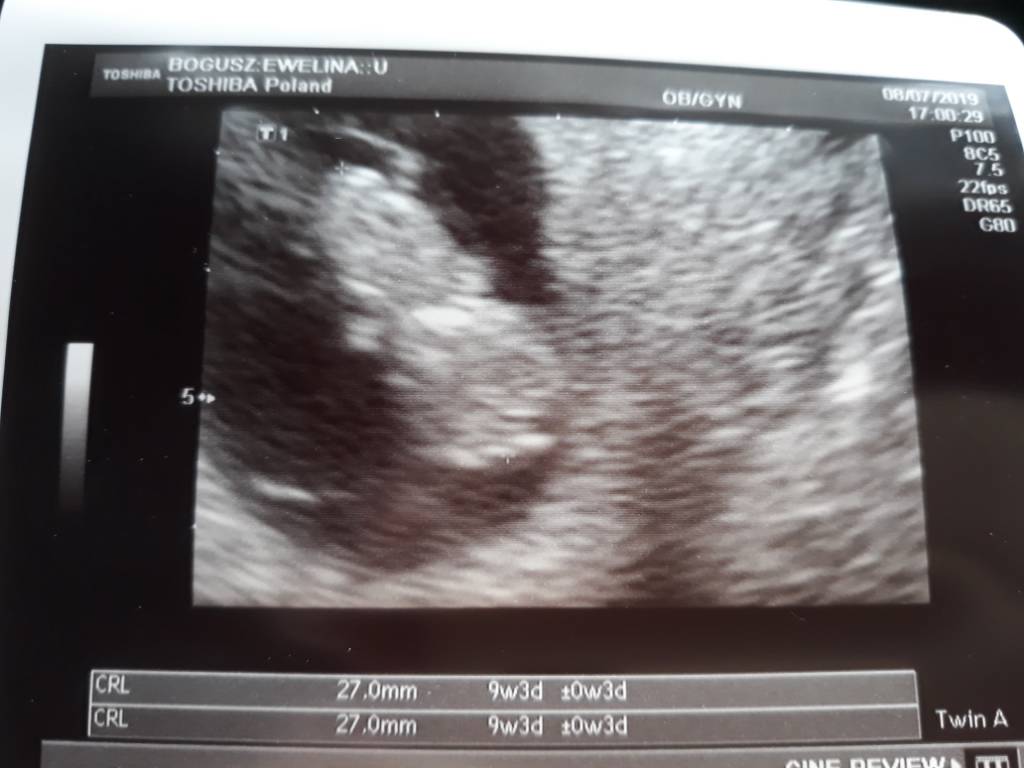

@Søde85 ale piękne zdjęcie z usg [emoji173]️ pewnie ze jestes juz nasza i nie oddamy